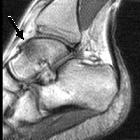

Bone stress

injury of the ankle in professional ballet dancers seen on MRI. Typical appearance of talar bone marrow edema observed on MR images of nine out of twelve ankles of symptomatic professional ballet dancers: Sagittal STIR (TR/TE = 1800/24) image of a 24-year-old male ballet dancer shows associated edema-type high signal within the talus (arrow).